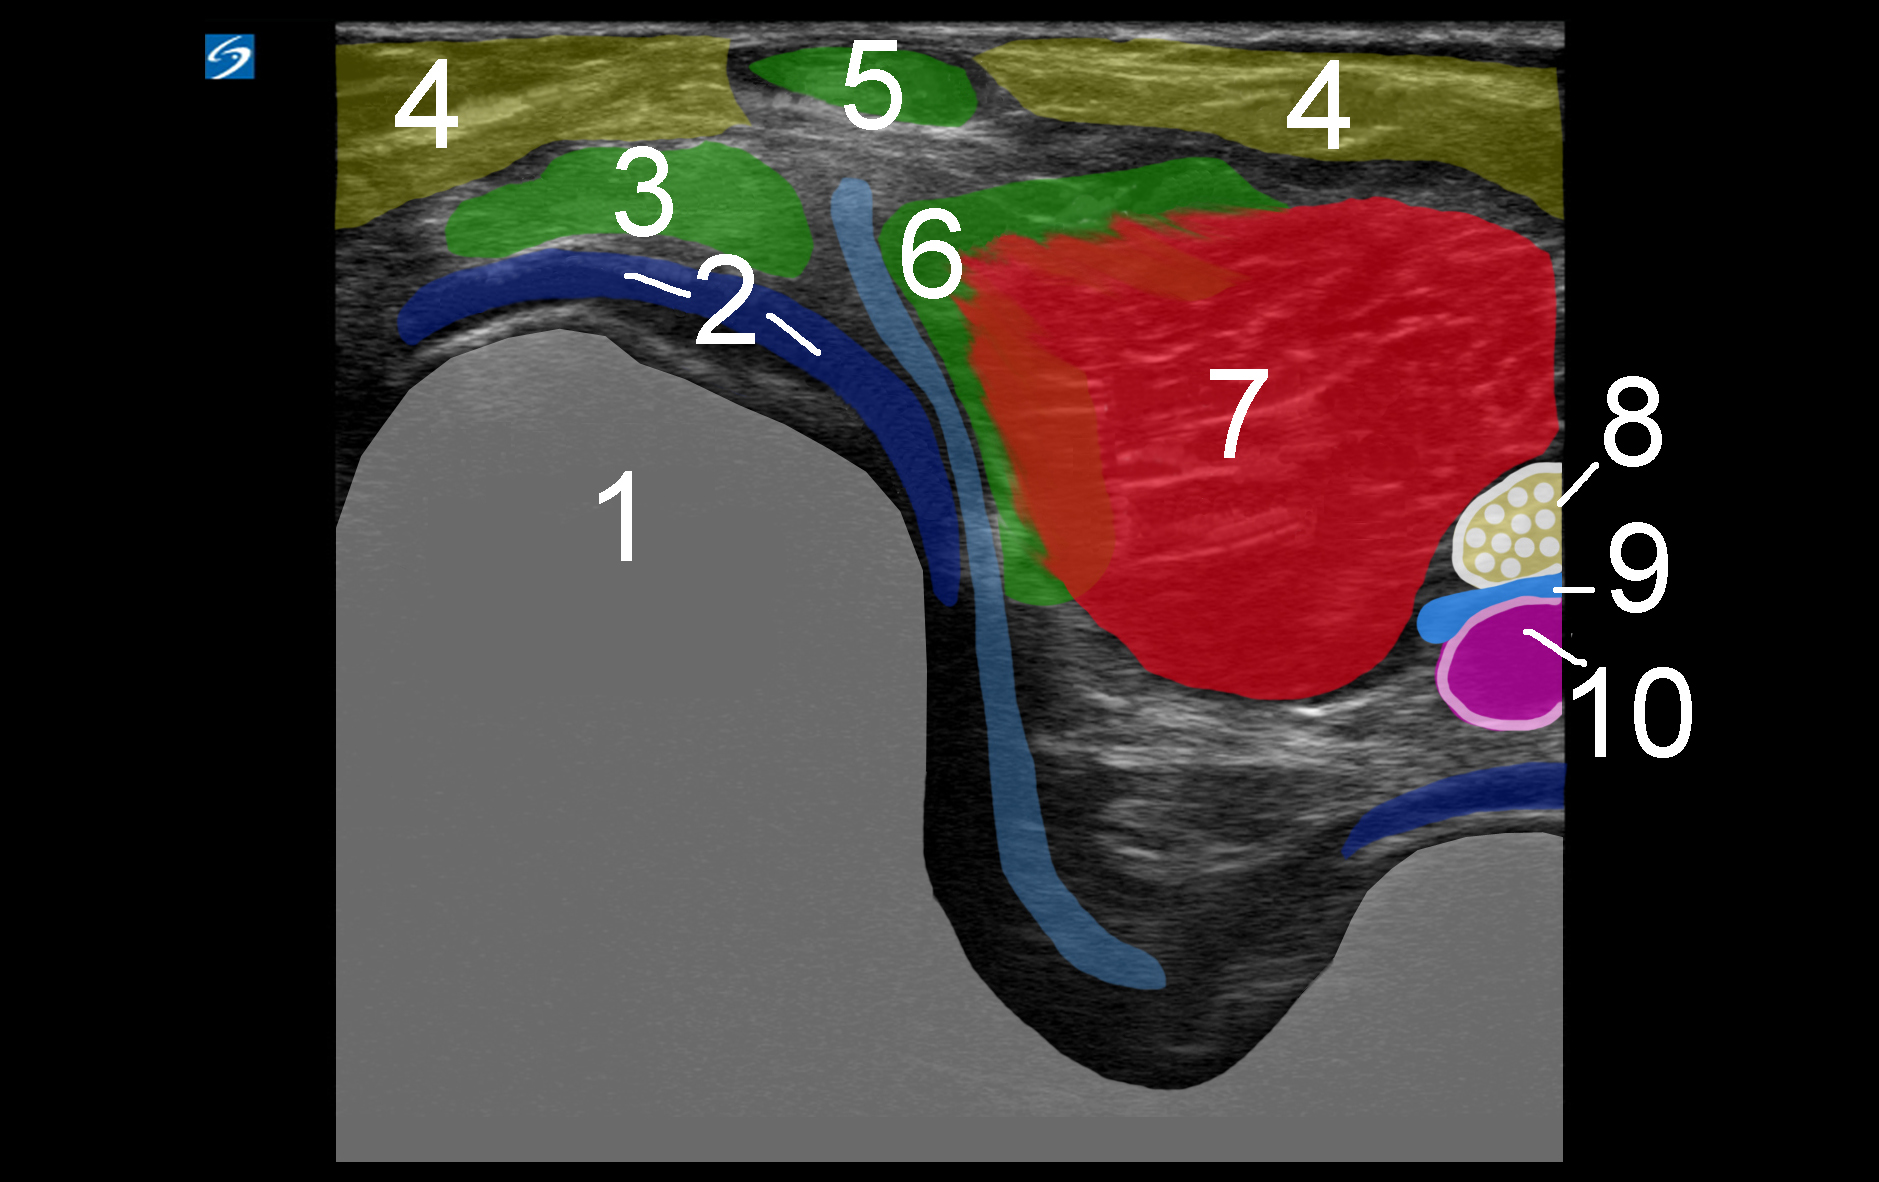

1. Medial Femoral Condyle

2. Articular Hyaline Cartilage

3. Semimembranosus Tendon

4. Adipose

5. Semitendinosus Tendon

6. Medial Head Gastrocnemius (MHG) Tendon

7. Medial Head Gastrocnemius (MHG) Muscle

8. Tibial Nerve

9. Tibial Vein

10. Tibial Artery